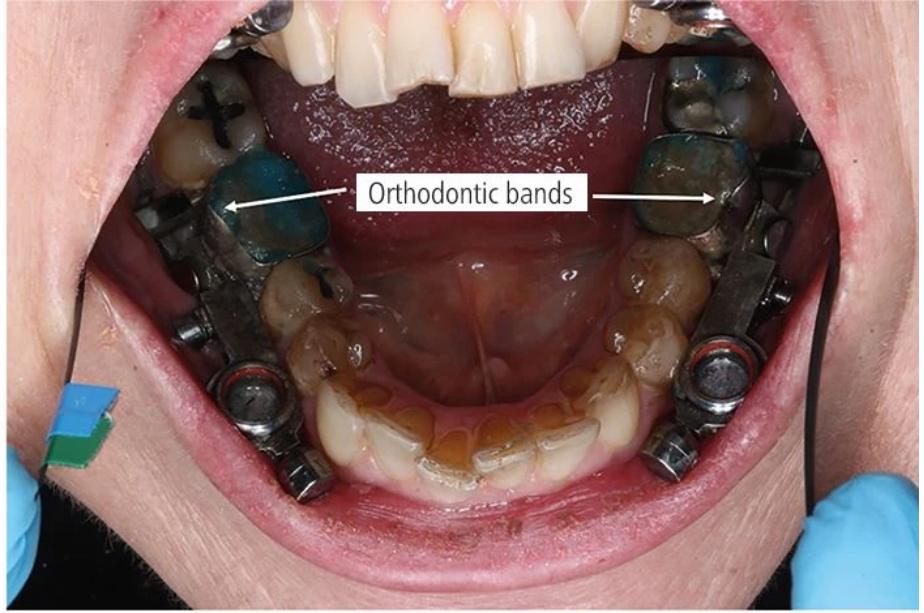

就是这么简单粗暴!这个装置名为Dental Slim Diet Control,看上去十分小巧,机器原理也很“简单粗暴”,通过安装在后排磨牙顶部和底部的磁性结构来限制使用者张开嘴巴的宽度,使其张嘴不超过2毫米——大概能塞下一根吸管的空间。奥塔哥大学研究人员称,这个装置可以有效地限制了参与者的流质饮食,同时不限制呼吸和言论自由。

装在真人牙齿里看起来是这样的